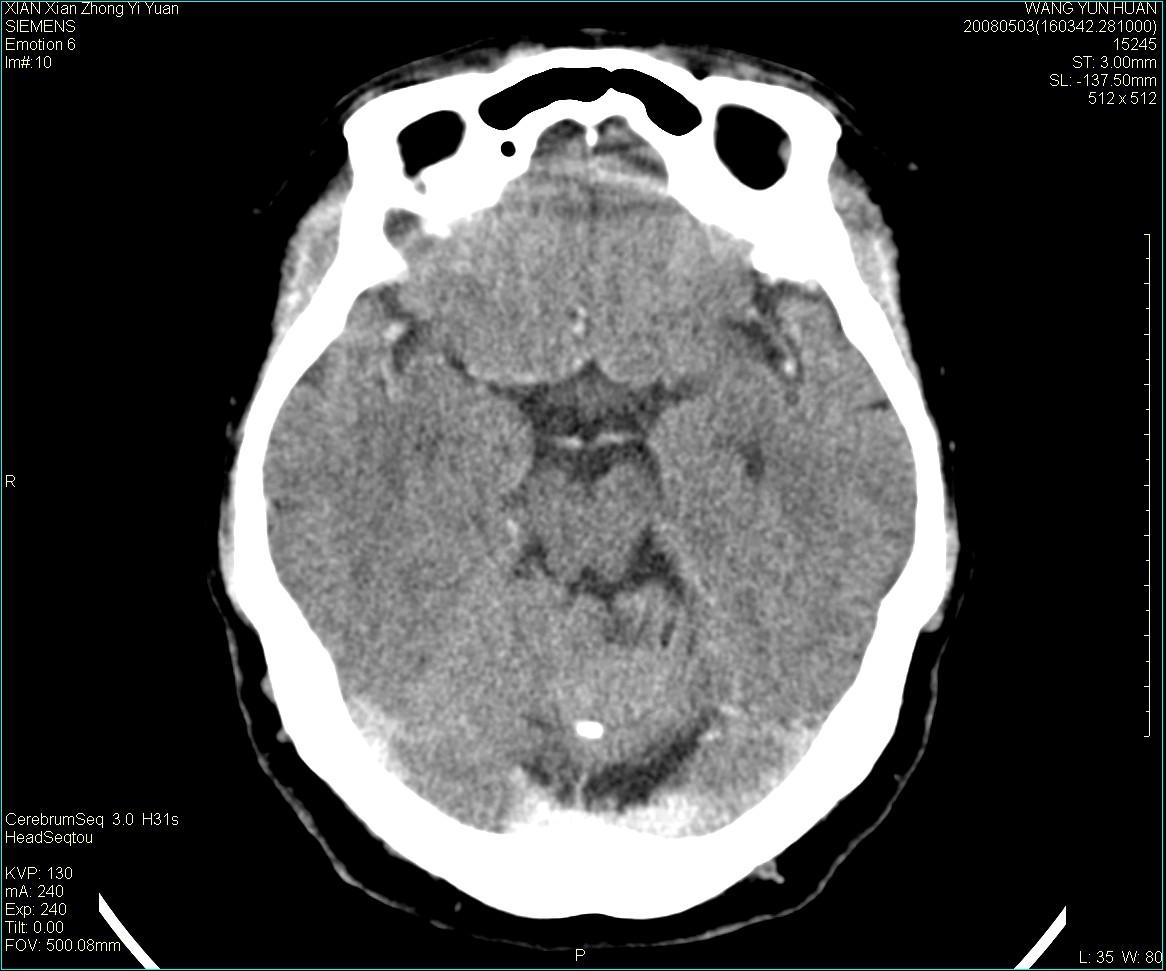

标题: CT13219:(补充强化)请会诊,患者女,60岁,头晕,大家看 [打印本页]

标题: CT13219:(补充强化)请会诊,患者女,60岁,头晕,大家看

病灶显示轻度强化,ct增加4hu左右,大家看是什么肿瘤.

强化后动脉期及延迟2分钟,五分钟图像

小脑蚓部囊型肿块,内有实性结节及钙化点。增强后囊壁及结节轻度强化。

考虑蚓部星形细胞瘤(ⅱ级可能性大)。

小脑蚓部肿块,周围无明显占位效应及水肿带,增强轻度强化,考虑低分级星形细胞瘤。